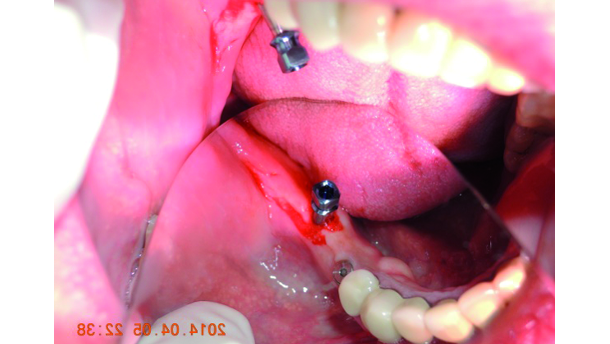

- 6 April 2014 implant placement 3.2 x 13 mm implant direct (Fig. 6),

When the bone width is narrow, periosteal elevation is recommended to be able to safely observe the osteotomic drills as they reach to the final depth. This procedure is only advised when a panoramic image is the only diagnostic tool we have as it adversely causes further bone loss during the healing phase.[13] In the present case, no periosteal elevation was performed (Fig. 6) and the patient did not have postoperative pain and swelling.